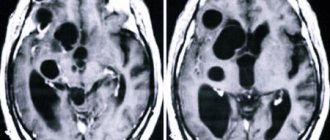

4. Для злокачественных опухолей головного мозга типично отсутствие чётких контуров и границ, напротив, их краёв не видно, они характеризуются инфильтративным типом роста (то есть распространяют свои клетки между клетками здоровой ткани — инфильтрация), некротический распад (в центре опухоль начинает пожирать саму себя за неимением питания, что приводит к области самопереваривания центральных участков опухоли), высокие темпы роста и развития (скоротечный драматический исход) и метастазирование (распространением опухоли в соседние участки мозга по оболочка и по спинно-мозговой жидкости).

Рис6. Злокачественная опухоль левой лобной доли с отёком, некротическим распадом и без отчётливых границ